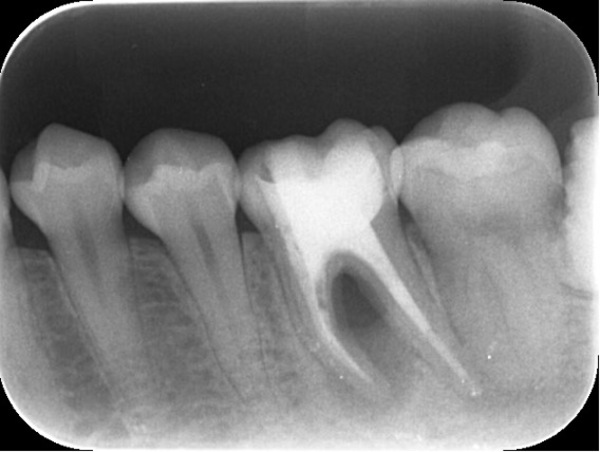

こちらが根管治療終了後のX線写真です。

治療開始時点で症状は和らいでおり、根管治療が終了した段階では完全に症状が消失しておりました。

通常であれば、ここから仮歯にて数カ月経過観察を行い、次の判断をしていきます。

仮止め6ヶ月後の経過観察写真です。患者様のご都合で少し間が空きましたが、その間も無症状でした。

こちらは比較用初診時X線写真です。

治療前後を比較してみると、順調に骨が回復してきていることがわかります。しかし、まだ根と根の間、根分岐部と呼ばれる部分の骨が完全には上がってきておりません。

このまま骨が上がらない可能性もありますが、今回は上がってくる可能性が高いと判断し、患者様とも確認をしつつ引き続き年単位で経過を見ていきます。